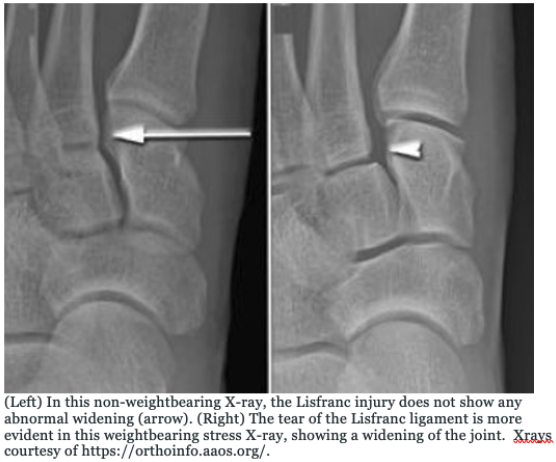

🦴Lisfranc injuries in peds:

- 💥direct blow to foot after jump/fall or forced dorsiflexion w/ rotational force

- pain/swelling at base of 1st/2nd metatarsal

- test by holding hindfoot, abduct/pronate the forefoot --> pain=concern

- 🩻 WEIGHT-BEARING films, AP/lat/oblique

#tilt